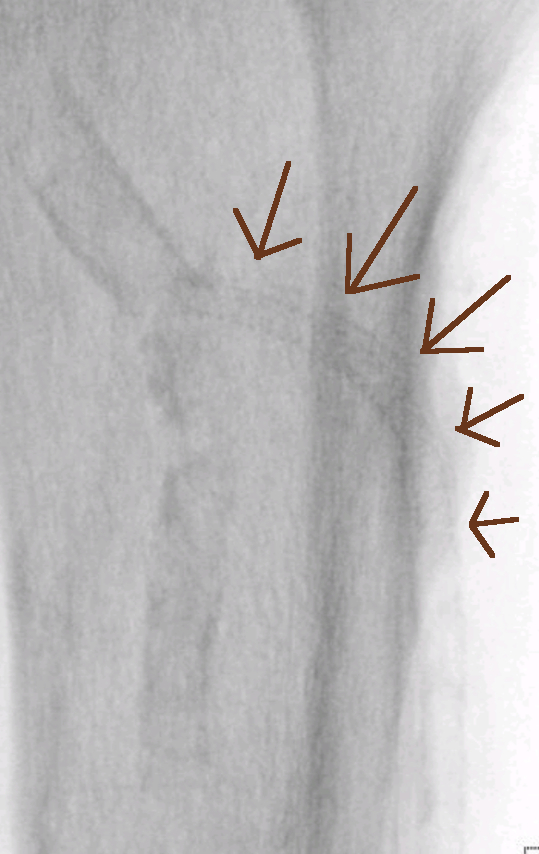

Žilna opornica je nameščena (rjave puščice), arterija je ponovno dovolj in dobro prehodna.